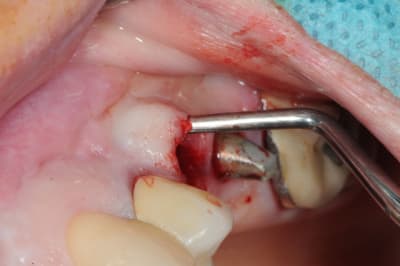

4-5: eh ben oui, elle est détruite! une simple curette insérée dans l'alvéole permet de visualiser l'importance de la perte osseuse vestibulaire.

que faire ??

1- curette en appuie sur la face vestibulaire montrant la destruction osseuse.